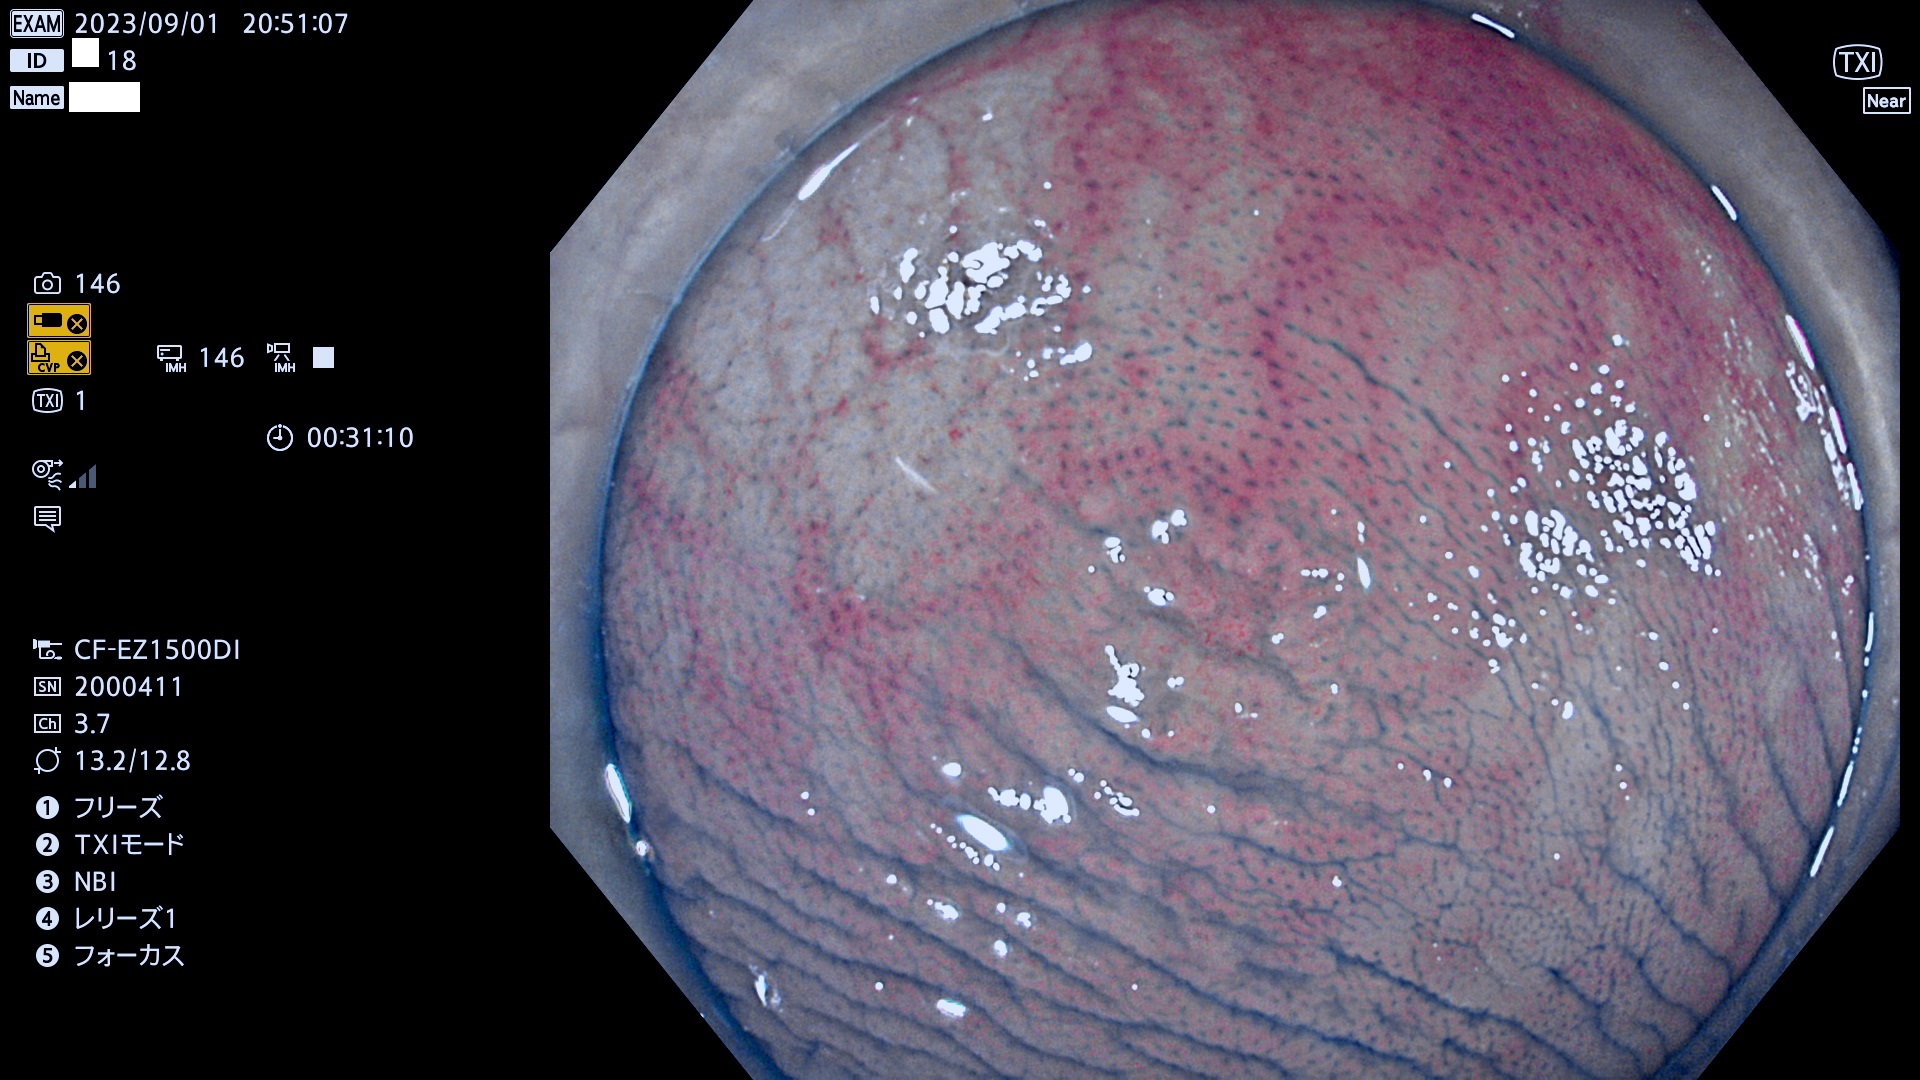

表面型腺腫(Flat Adenoma)の中で、完全に平坦な物をUb、陥凹している物をUcと呼びます。平坦隆起型(Ua)よりも、発見が難しく危険な病変です。このタイプは「内視鏡後・大腸癌の重要犯人」であり、この発見率は「腺腫発見率」よりも、重要な意味があります。

毎週の検査(木・金・土・日)に発見されたUb、Uc型・腺腫を、その週の日曜の夜にUPし1週間、提示します。

抽出の対象期間 2023年8月31日(木)〜9月3(日)の4日間(48件の検査)12件